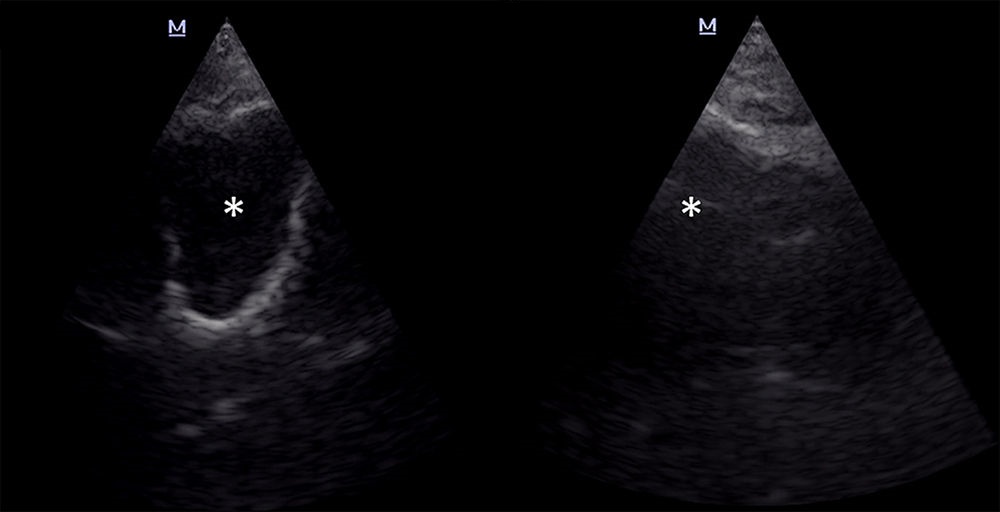

Делают узи носа

Делают узи носа 56 фотографий